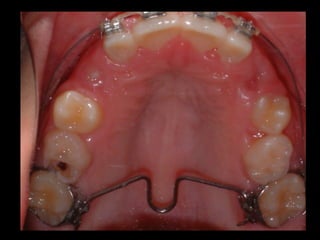

Cuando solo quiero torque, la BTP debe quedar lo más cercana al paladar, porque  cuanto mas largo sea el brazo mejor puede actuar.

Cuando necesito intrusión más torque, primero intruyo, y después torqueo porque si no, las cúspides palatinas se anclan en la cortical y no puedo intruir.

CUANDO LOS MOLARES TIENEN TORQUE +, LOS TUBOS PALATINOS ESTÁN  INCLINADOS HACIA OCLUSAL Y VESTIBULAR, SE CREA UNA DIVERGENCIA ENTRE LAS  LLAVES DE LA BARRA, QUE SON PARALELAS EN SENTIDO VERTICAL, Y LA INCLINACIÓN  DE LOS TUBOS PALATINOS.  ESTO PRODUCE UN EFECTO DE TORQUE -, LA ELEVACION DE LAS CUSPIDES PALATINAS Y CON ELLO EL CONTROL  OCLUSAL DEL SECTOR  POSTERIOR .

PARA QUE SE PRODUZCA UN TORQUE – ADECUADO, LA LLAVE DEBE POSICIONARSE  5-6 mm HACIA OCLUSAL DEL TUBO PALATINO DEL MOLAR DEL LADO OPUESTO .

Cuando solo quierotorque, la BTP debe quedar lo más cercana al paladar, porque cuanto mas largo sea el brazo mejor puede actuar.

Cuando necesito intrusiónmás torque, primero intruyo, y después torqueo porque si no, las cúspides palatinas se anclan en la cortical y no puedo intruir.

CUANDO LOS MOLARESTIENEN TORQUE +, LOS TUBOS PALATINOS ESTÁN INCLINADOS HACIA OCLUSAL Y VESTIBULAR, SE CREA UNA DIVERGENCIA ENTRE LAS LLAVES DE LA BARRA, QUE SON PARALELAS EN SENTIDO VERTICAL, Y LA INCLINACIÓN DE LOS TUBOS PALATINOS. ESTO PRODUCE UN EFECTO DE TORQUE -, LA ELEVACION DE LAS CUSPIDES PALATINAS Y CON ELLO EL CONTROL OCLUSAL DEL SECTOR POSTERIOR .

PARA QUE SEPRODUZCA UN TORQUE – ADECUADO, LA LLAVE DEBE POSICIONARSE 5-6 mm HACIA OCLUSAL DEL TUBO PALATINO DEL MOLAR DEL LADO OPUESTO .